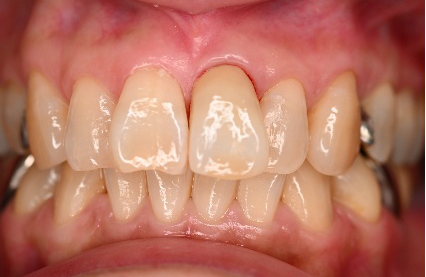

治療内容

前歯3本にオールセラミック冠を被せて、歯並び及びすり減った歯を審美的に回復しました。歯ぎしりが強くあることがわかりましたので、マウスピースを使ってもらう事にしました。

所感

一番オススメな方法は、矯正をし、歯並びを整えた後、すり減って形が変わってしまった歯に被せ物をすることをお話ししました。患者さんは、3本に被せ物をすることにより歯並びをきれいにすることを希望されました。

治療後、「曲った前歯が長年コンプレックスでした。セラミックの歯の色合いや形が自然な仕上がりで、相談して本当に良かったです!神経を抜くこともなく治療ができ、予定よりも低料金にしてもらえたのがありがたかった。先生も、歯科衛生士さんも事務の人も皆、優しく寄り添った対応をしてくれました。ありがとうございました!」と、とても嬉しいお話しをしてくださいました。

オールセラミック冠3本:¥93,500(生活歯)×3本=¥280,500(税込)

Before

After